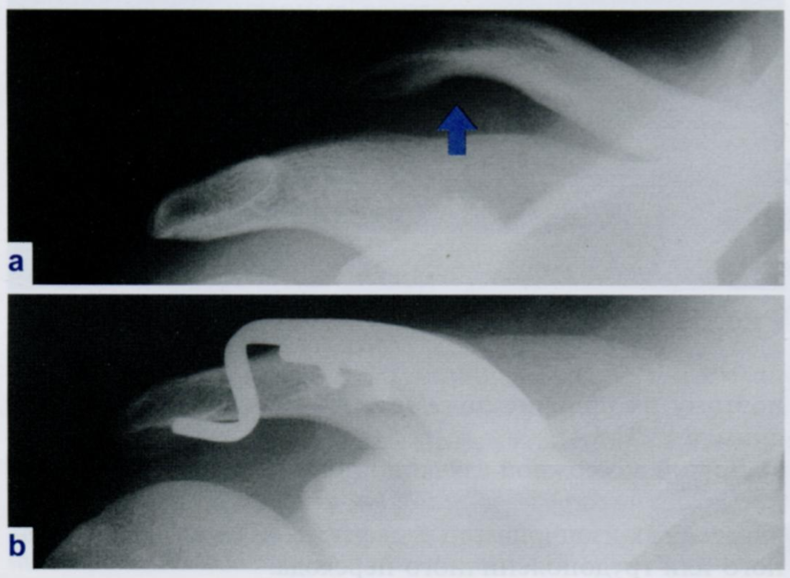

На снимке мы видим акромиально-ключичное соединение. Попытайтесь разобраться, какое повреждение тут можно увидеть.

Разрывы каких связок наиболее типичны в данной структуре (2)? Как выглядят на Rx снимке? Какие классификации данной травмы существуют?

Что мы видим на снимке b?

На снимке мы видим разрыв связок между ключицей и клювовидным отростком (посмотрите на картинке анатомию клювовидно-ключичной связки) или между ключицей и акромионом.

При этом сокращение грудинно-ключично-соцевидной мышцы тянет ключицу вверх, формируя видимую ступеньку клинически и на Rx (снимок “а”). При этом, если мы давим на ключицу, она опускается вниз и затем возвращается назад под тягой мышцы (симптом “клавиши пианино”).

Существуют классификация Тосси и Роквуда. Выполняют повторно снимок области, при этом пациент держит по 5 кг. гире в каждой руке для смещения акромиона вниз, и уже по изменениям/отсутствию изменений классифицируют перелом, и можно точнее понять, какие связки разорваны.

На снимке “b” мы видим фиксацию разрыва/перелома крючковидной пластиной.